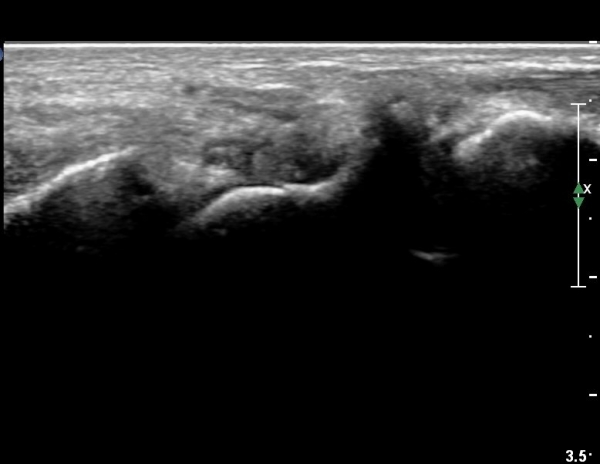

È®ÁøÀ» À§ÇÑ ÃÊÀ½ÆÄ°Ë»ç¿¡¼ ÁÖ»ó°ñ °ñÀý È®ÀÓ µÊ.

ÁÖÁöÇÏ´Ù½ÃÇÇ ÁÖ»ó°ñ °ñÀýÀº ´Ü¼ø¹æ»ç¼±°Ë»ç¿¡¼ È®ÀεÇÁö ¾Ê´Â °æ¿ì°¡ ÈçÇѵ¥

ÃÊÀ½ÆÄ°Ë»ç¸¦ ½ÃÇàÇÏ¸é ¹Ì¼¼ÇÑ °ñÀýµµ Áø´ÜÀÌ °¡´ÉÇÏ´Ù. |